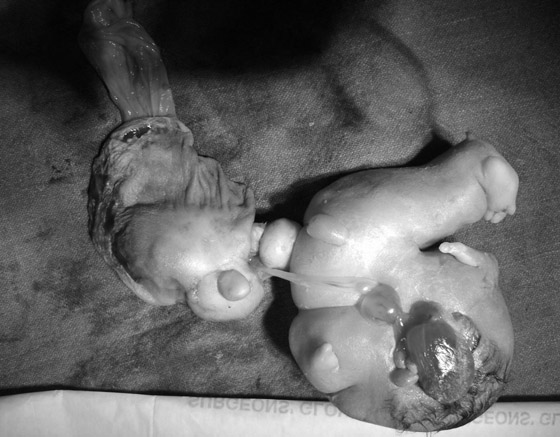

3- التوأم المغاير الخارجي:

حوالي 10 في المائة من التوائم السيامية يعتبرون توائم مغايرة خارجية. بشكل أساسي، لا يتطور لدى أحد الشقيقين التوأم جميع أعضاء الجسم، لذا يعتمد على الثاني للاستمرار والبقاء. قد يبدو هذا النوع من التوأم المتناظر غير مكتمل النمو أقرب لطفرة منه إلى توأم متصل. من بين حالات هذا النوع من التوائم كلب ولد مع ذيل بارز من رأسه، الذي هو في الواقع توأم مغاير خارجي غير مكتمل النمو.

تماما مثل التوائم السيامية الأخرى، لطالما افترض العلماء والباحثون أن هذا النوع من التوائم يحدث عندما ينقسم الجنين في وقت متأخر ولا ينقسم بشكل مثالي، ولسبب من الأسباب يكون الانقسام أيضًا غير متكافئ ولا متكامل، لذا لا يتطور أحد التوأم بشكل كافي للبقاء والاستمرار اعتمادا على نفسه، أو يكون في المجمل عبارة عن جزء من شخص آخر متصل بشقيقه التوأم. قد يفسر هذا النوع الملتوي من الانقسام سبب بروز ذيل من رأس الكلب الذي ذكرناه سابقًا.

لكن بعض حالات وقوع هذا النوع من التوائم عند البشر قد تدعم نظرية الالتحام أكثر، والمشكلة الأكبر هي أنه لم يسبق لأحد أن رأى الانقسام وهو يحدث، حيث لم نشهد على الإطلاق انقسام جنين إلى جنينين اثنين، مما يعني أننا لم يسبق لنا أن أكدنا فكرة أن توقيت انقسام الجنين قد يكون له أي تأثير، كما أننا لا نعلم بشكل مؤكد بأن الجنين قد ينقسم بشكل جزئي أو غير متكافئ ومع ذلك ينجح في البقاء على قيد الحياة.

لكننا اقتربنا بشكل أكبر من ذلك بكثير للحصول على دليل على وقوع الالتحام بين الأجنة داخل الرحم، وذلك بفضل حالة توأم مغاير خارجي تم نشرها سنة 1997. ولد هذا الطفل الذي تناولته الدراسة بما يبدو وكأنه زوج من السيقان بارز من صدره، لكن تلك الساقان لم تكن له، حيث اكتشفت الاختبارات والفحوص الجينية بأن الساقان تعودان لتوأمه الأخوي، والذي إن كان صحيحا قد يعني أن جنينين منفصلين تلاحما في مرحلة ما داخل الرحم.

بالطبع كانت تلك حالة واحدة فقط، لكنها تقترح أن الأبحاث على هذا النوع من التوائم قد تساعد على تسوية الجدل حول الانقسام/ الالتحام، أو أن يثبت أن كلا من النظريتين صالح وكلا الظاهرتان قابل للحدوث. في جميع الحالات، سيمنح الباحثين فهما أفضل حول سلوكات الخلايا البشرية أثناء تطورها، وهو ما قد يساعد بدوره الأطباء على علاج حالات مرضية حيث لا يجري التطور وفقا ما هو مخطط له.